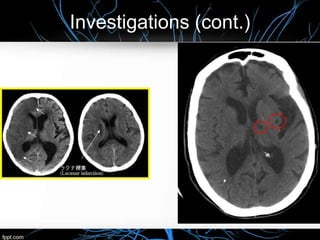

Infarction appears as hypodense (more dark) area on CT

Hemorrhage appeare as hyperdesne (bright) area on CT